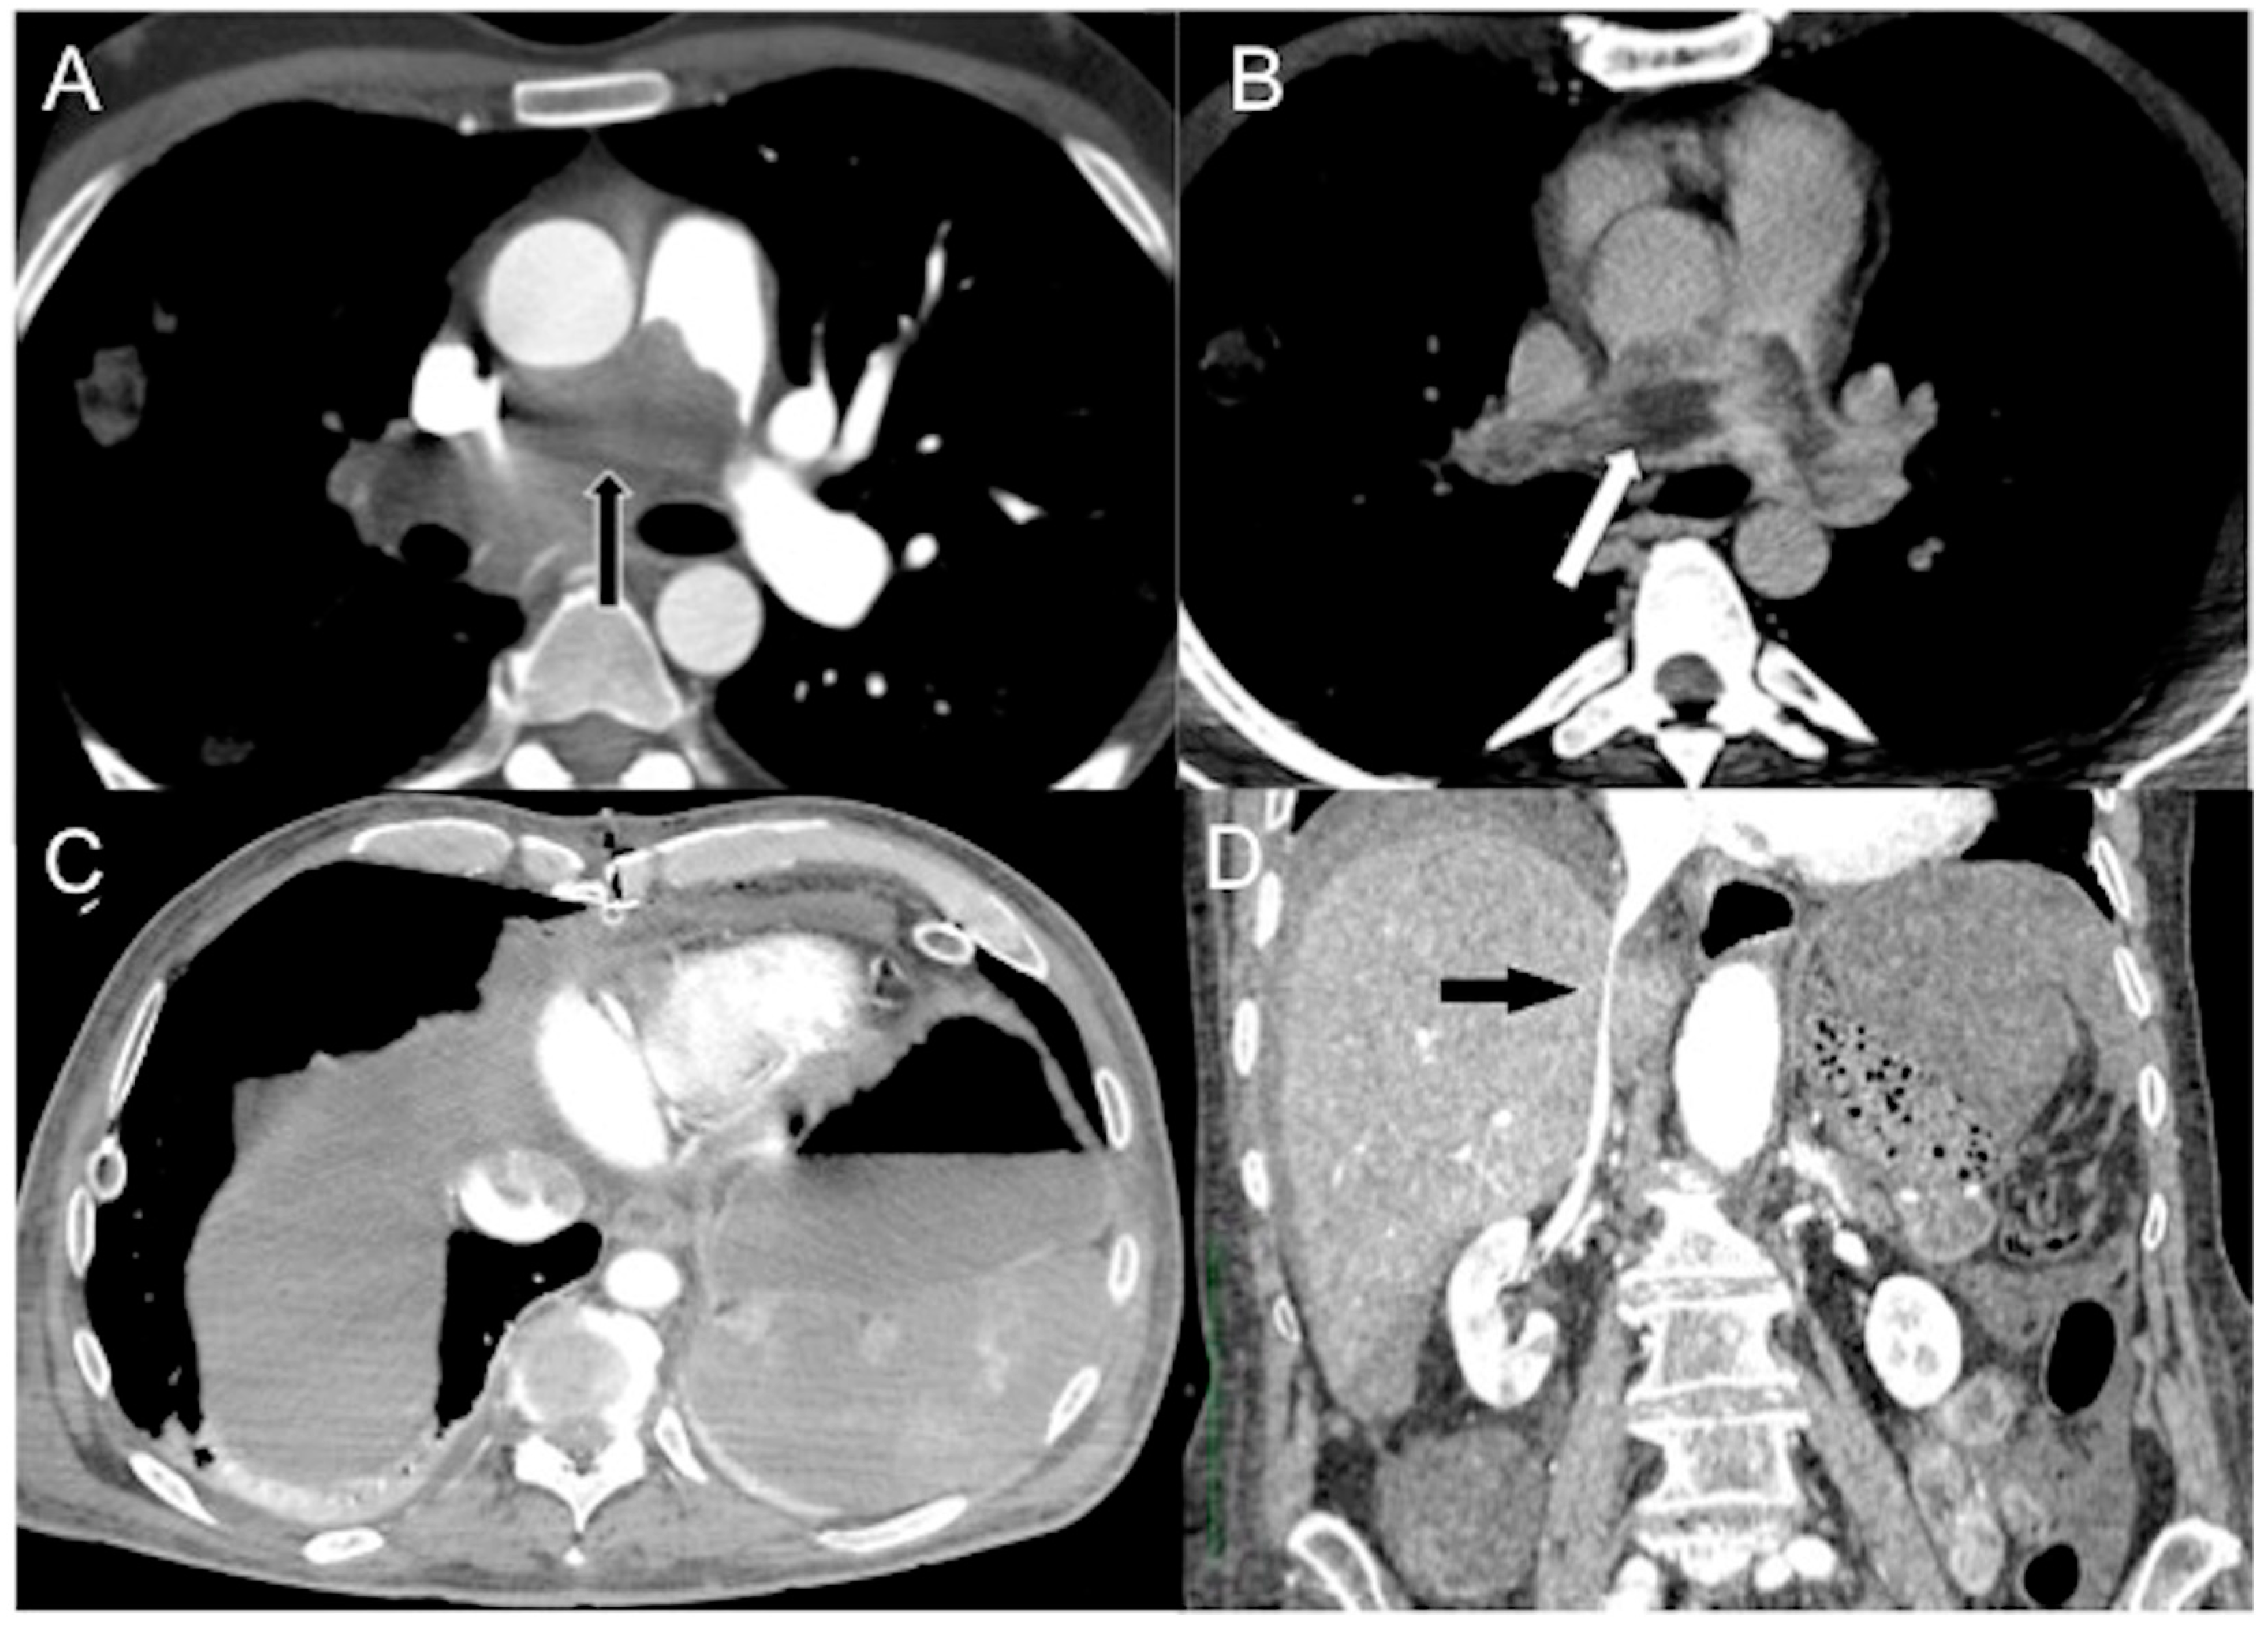

- In a state of advanced hemodynamic instability, many homeostatic mechanisms try to maintain arterial pressure and adequate tissue perfusion to critical organs, such as the brain and heart, by reflex stimulation of the sympathetic nervous system, elevated levels of angiotensin II, adrenaline, and noradrenaline, and vasoconstriction (compensated shock). Carotid baroreceptors respond to decreased blood pressure by triggering increased sympathetic signaling and maintaining cardiac output (sympathetic “fight or flight” response). In cases of decompensated shock, when compensatory mechanisms falter and prior to the onset of death, the pumping action of the heart ceases, leading to a substantial decline in systemic arterial and venous pressures. Consequently, the arteriovenous pressure gradient diminishes [6,41,42]. This altered hemodynamic state results in stasis of CM in the venous system in the presence of the left chamber and arterial opacification, and of other infrequent and often unappreciated ominous MDCT vascular signs that represent a true hypovolemic state and must be recognized early by the radiological staff to improve survival [24,43,44,45,46,47,48]. This may be called the “venous CM pooling and layering” pattern, indicating that compensatory mechanisms are becoming insufficient and the patient must receive immediate treatment.

- In irreversible end-organ dysfunction, injected IV CM circulation is supported only by the pressure applied by the automated power injector and the density of contrast material. Circulatory arrest leads to dense contrast pooling and layering in the SVC, IVC (inferior vena cava), and right heart chambers with non-opacified left heart chambers or arterial vessels (Figure 1) [43,45,49,50,51,52]. This may be called the “non-beating heart” pattern. Cardio-pulmonary aggressive resuscitation must immediately be initiated within the framework of a predetermined emergency plan.